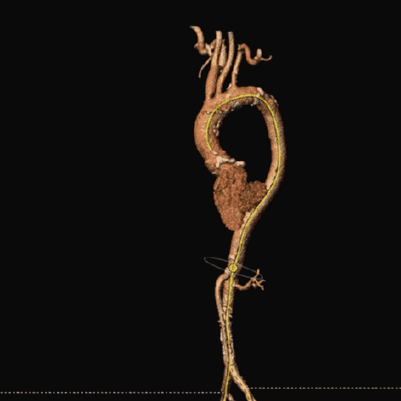

主动脉根部解剖

三叶式主动脉瓣,轻度钙化,钙化分布均匀,多位于瓣叶附着缘处血管内壁。主动脉瓣瓣环周长80.9mm,平均周长径25.7mm。瓦氏窦内径可。

左冠开口高度17.9mm,右冠高度19.5mm,冠状动脉散在钙化。

瓣环上及主动脉解剖

血管入路解剖

外周入路血管散在钙化,双侧髂外动脉管径处于临界范围